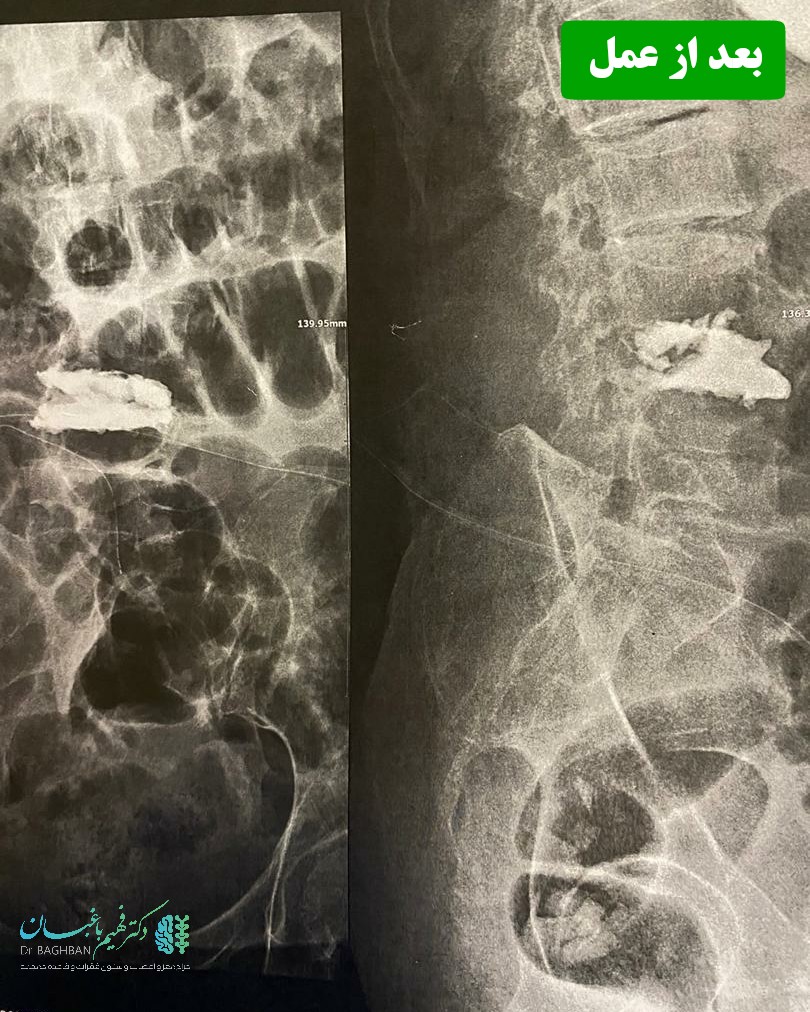

خانم ۸۴ ساله که با درد شدید کمر و ناتوانی در راه رفتن و سوزش و کرختی پاها مراجعه کردند. بیمار دچار شکستگی مهره L4 شده بود که سبب تنگی شدید کانال شده بود. بیمار تحت عمل جراحی جهت کاهش فشار از ریشه های عصبی و تزریق سیمان جهت بازسازی و استحکام مهره L4 قرار گرفت.

بعد از جراحی تزریق سیمان

بعد از عمل